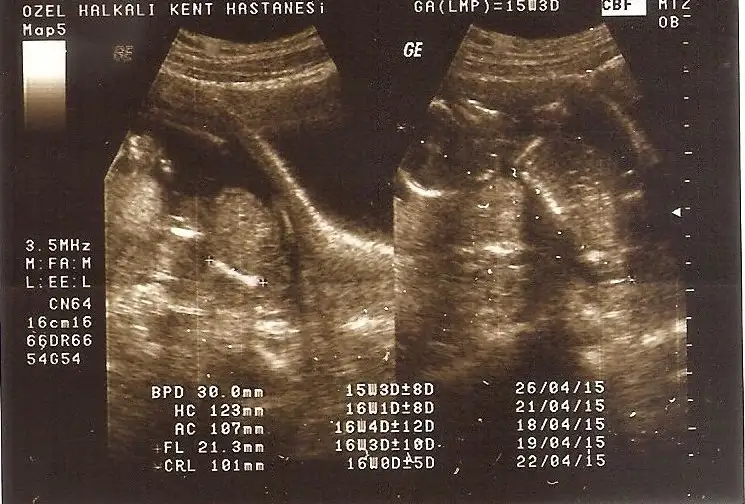

Diğer ultrason görüntülerini atıyorum, lütfen bide bunlara bakarmısın?

Eki Görüntüle 1277161 Eki Görüntüle 1277162